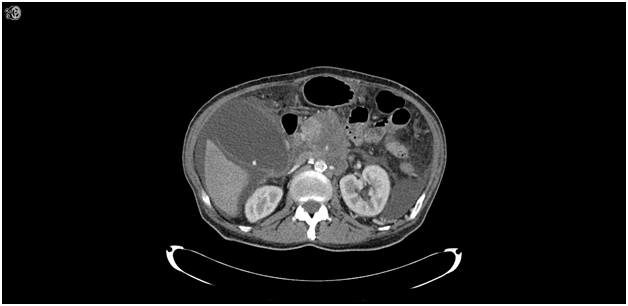

The patient underwent a complete blood count (CBC) draw and complete metabolic profile (CMP). His laboratory data revealed a total white blood cell count of 13.2 K/uL, hemoglobin (Hgb) of 11.0 g/dL, and a platelet count of 211 K/uL. His differential was 78.1% neutrophils with a total absolute neutrophil count (ANC) of 10.31 K/uL. Other than his sodium level that was 130 mmol/L, glucose 136 mg/dL, albumin 2.4gm/dL, and total protein of 5.8 gm/dL the patient’s metabolic profile was normal. The patient consented to a clinical trial and proceeded with screening. His screening visit was the following week on 1/22/14 where he noted a persistent right-sided abdominal pain that was characterized as dull and constant without any radiation. The patient’s vitals were noted to be a blood pressure of 107/57 mmHg, pulse 113 b/min, temperature of 99.1 Fahrenheit, and oxygen saturation of 96% on room air. The patient’s physical examination was unchanged with continued tenderness in the epigastric and now right upper quadrant abdominal region but the patient has no evidence of distention and normal bowel sounds. A CBC and CMP were drawn again that day. Several changes were noted in the patient’s labs: his WBC had increased to 23.2 K/uL with an ANC of 20.19 K/uL, a total bilirubin of 2.4 mg/dL, an alkaline phosphatase of 141 U/L, and a direct bilirubin of 1.3 mg/dL. The patient also has a urine analysis done showing brown, cloudy urine, with a specific gravity of 1.025 and positive for bilirubin, protein, and several bacteria with negative nitrites, negative wbc, and negative leukocyte esterase. Due to patient’s increased abdominal pain from one week ago his narcotic frequency with short acting dilaudid was increased from twice a day as needed to every 3 hours as needed and remained on his prior dose of fentanyl pain patch of 100 mcg every 72 hours. The patient was scheduled for a CT scan later that day. CT scan with IV contrast was done of the chest/abdomen/pelvis which showed a hugely distended gallbladder with a thin wall and acute cholecystitis secondary to malignant bile duct obstruction (Figure 1). The patient was subsequently admitted for IV antibiotics and underwent an emergent laparoscopic cholecystectomy.

Figure 1 Axial CT image showing marked distension of the gallbladder 7.5 x 12 cm with mild diffuse wall thickening consistent with acute cholecystitis. Gall stone also noted along with abdominal ascites. His pancreas cancer lesion is also shown in the center of the image.

To date there have been no published reports regarding attenuation of symptoms in patients presenting with acute cholecystitis following celiac plexus nerve block. In our patient, his clinical presentation was not consistent with acute cholecystitis outside of leukocytosis and slight elevation in liver enzymes, which are non-specific findings. The patient did not exhibit a positive Murphy’s sign and was afebrile. The CT scan showed a hugely distended thin walled gallbladder with an impending perforation and remarkably the patient had minimal symptoms. Our case does illustrate the need for further investigations, especially in cancer patients with a history of celiac plexus blockade present in a clinical setting with new onset abdominal pain. Physicians should have a low threshold in this specific patient population to order diagnostic studies to rule out acute abdomen infections such as acute cholecystitis.